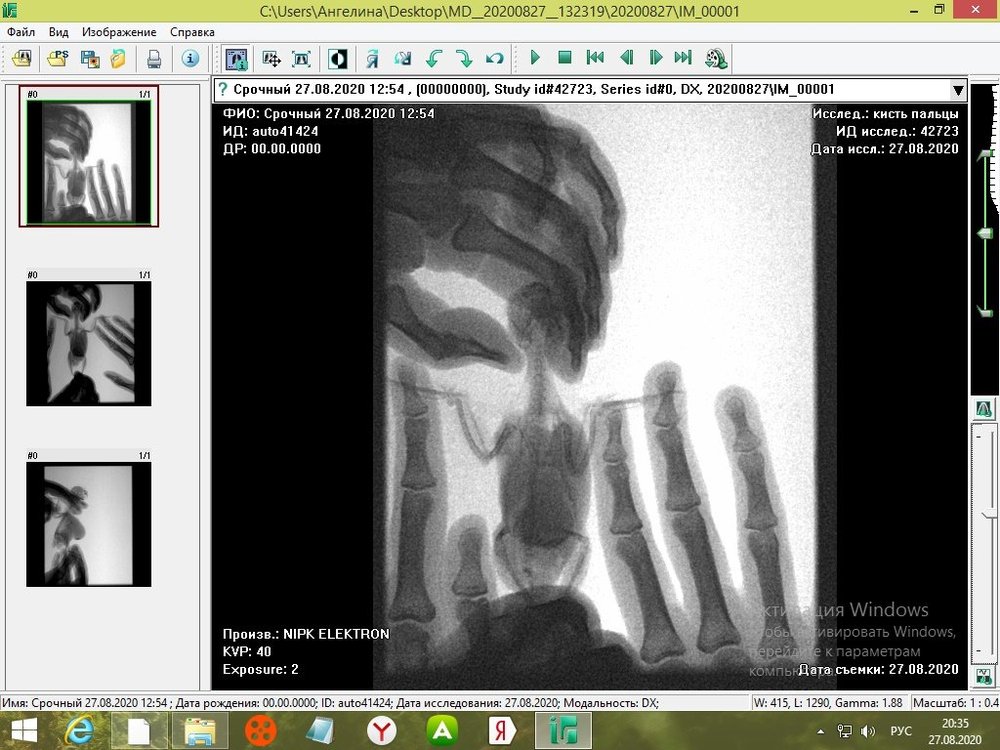

tanushka-sol2020 Опубликовано 27 августа, 2020 Автор #15 Опубликовано 27 августа, 2020 Некадрированные исходные снимки --- щёлкните полосу ниже. Скрытый текст

Кузяныч Опубликовано 28 августа, 2020 #16 Опубликовано 28 августа, 2020 Ох, бедная волнушка... В помёте на шли бактерии (++), слизь (+), жир (+), клетчатку (++)... Есть и непонятные для меня записи... По рентгену на втором снимке справа мне видится что эта огромная припухлость --- растянутый зоб... 18.08.2020 в 17:16, tanushka-sol2020 сказал: Что за опухоль? Она в моих руках меняется: то сморщится, то раздувается как шар надувной... Неужели, действительно зоб?... @tanushka-sol2020, срочно звоните Зосе, просите посмотреть снимки. Мазок из клюва... уф-ф... не знаю пока на сколько он нужен... Если на нистатине птице легче, то давайте его --- придерживайтесь дозировок, что давала вам Зося. Расположите лесенку горизонтально чтоб попугайчик экономил силы. Установите всё как можно ниже к полу. Проверьте, чтоб птичка не пыталась лезть выше и не висла на стенке. Помёт оранжевый... возможно, действительно, печень страдает... Карсил не отменяйте... За гепатовет и как вообще быть я не могу сказать. Нужно чтоб Зося посмотрела рентген. Свяжитесь, пожалуйста, с ней. У меня такое впечатление, что у этой волнушки растянут зоб и от этого плохо уходит и застаивается, протухая, пища.

tanushka-sol2020 Опубликовано 28 августа, 2020 Автор #17 Опубликовано 28 августа, 2020 (изменено) @Кузяныч К сожалению, от нистатина у нее сильно страдает печень. Я не стала ей давать, почти 3 недели принимали. Но срыгивание снова вернулось. Когда я собирала мазок из глотки, она потом срыгнула на одежду. Капли были песочного цвета и консистенция, как каша жиденькая. Но с запахом. Переживаю, вдруг неправильно сделала мазок, впервые же. Во вторнике будет готов анализ. Отпишусь. Рентген делали в больнице, я их кое-как уговорила. Первый "блин с комом", тоже выложила. Вдруг качества нет на снимке, что показал. Завтра Зосе позвоню. Спасибо, что ответили. Эти снимки неудачные выше, племянница скидывала. Я немного контраст отрегулировала, чтобы было видно. Изменено 28 августа, 2020 пользователем tanushka-sol2020